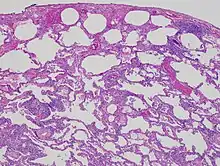

High magnification photomicrograph of a lung biopsy taken showing chronic hypersensitivity pneumonitis (H&E), showing mild thickening of the walls of the small air sacs by invasion of white blood cells. A multinucleated giant cell, seen within the walls of the air sacs to the right of the picture halfway down, is an important clue to the correct diagnosis.

Low magnification view of the histology of chronic hypersensitivity pneumonitis. The interstitium is expanded by a chronic inflammatory infiltrate. Two multinucleated giant cells can be seen within the interstitium at left, and a plug of organizing pneumonia at bottom left.

Lung biopsies can be diagnostic in cases of chronic hypersensitivity pneumonitis, or may help to suggest the diagnosis and trigger or intensify the search for an allergen. The main feature of chronic hypersensitivity pneumonitis on lung biopsies is expansion of the interstitium by lymphocytes accompanied by an occasional multinucleated giant cell or loose granuloma.[7][22]

When fibrosis develops in chronic hypersensitivity pneumonitis, the differential diagnosis in lung biopsies includes the idiopathic interstitial pneumonias.[23] This group of diseases includes usual interstitial pneumonia, non-specific interstitial pneumonia and cryptogenic organizing pneumonia, among others.[7][22]